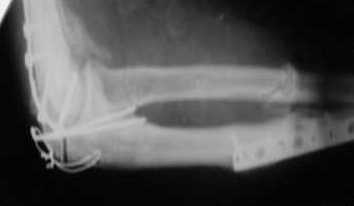

Уважаемые коллеги! Нужен Ваш совет, Подскажите пожалуйста, как можно в дальнейшем этому больному помочь. В марте первая операция, пришлось оперировать на 16 сутки в виду инфицированных садин и анемии. Заживление первичным натяжением,раняя разработка после операции, а через 2 нед болевой синдром,и постепенно движения в локтевом суставе ограничились до полного анкилоза. Повторно через 4 месяца вторая операция" артролиз,удаление оссификатов, удаление фиксаторов, реостеосинтез этой же реконструкционной пластиной и винтом" интраоперационно после удаления оссификатов и фиксаторов обнаружил, что перелом не сросшиеся, поэтому пришлось синтезировать заново. Зажило рана первично, объем движений в локтевом суставе сгибание 70, разгибание160, ротационные движения востановились полностью,вроде бы успокоились. Опять постепенно в течении 8 нед после повторной операции постепенно движения ограничились до 80 - 110, на снимке оссификат. Снимки во вложении, буду рад Вашим советам. Спасибо!С уважением Шухрат.